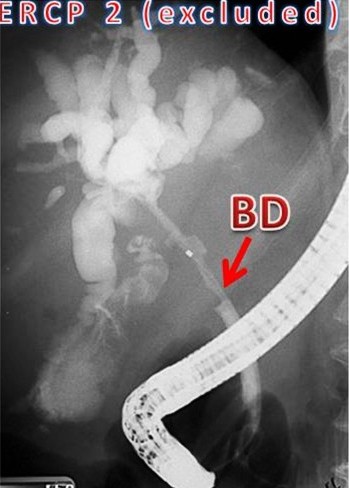

The reporting of the ERCPs was done in a stepwise fashion. The first step was to identify ERCPs in which both ducts were filled and pancreaticobiliary confluence was clearly identified in more than one image (inclusion criteria for study) (Figure 1). ERCPs in which only one duct (pancreatic or biliary) was filled or the confluence of the pancreatic and bile ducts was not clearly visualized were excluded from the study (Figure 1). Second, in those ERCPs included in the study, we then reported on whether the pancreatic and bile ducts opened into the duodenum separately or if the ducts were joined to each other and a common channel opened into the duodenum(Figure 2). Third, we measured the length of the common channel in the latter (Figure 3). To do so, we measured the actual length of the channel as it appeared on the images and corrected it with a magnification factor, as determined by the actual and imagined (as on images) width of the endoscope [15, 21]. If the corrected length of the united duct was less than 6 mm, it was reported as a short common channel. If the corrected length of the united duct was between 6 and 15 mm, it was reported as a long common channel. If the corrected length of the common channel was more than 15 mm, it was presumed that the ductal union had occurred outside the duodenal wall and such patients were reported as having anomalous pancreaticobiliary ductal union [20, 22]. For patients with anomalous pancreaticobiliary ductal union, we determined the pattern and angle of the ductal union. Anomalous pancreaticobiliary ductal union was reported as P-B type when the pancreatic duct appeared to join the bile duct and B-P type when the bile duct appeared to join the pancreatic duct. The angle of union was the actual angle at which the union occurred between two ducts [23].

Figure 2. Step 2 of the present study classified the ERCPs into those with a separate opening and those with a common channel. On the left, ERCP image from a patient with alcohol-induced chronic pancreatitis. The bile duct (BD) and the pancreatic duct (PD) can be clearly seen and join the duodenum (arrows) without joining each other. On the right, the image belongs to a patient with choledocholithiasis. The pancreatic duct (PD) and the bile duct (BD) join each other to form a long common channel (13 mm) which enters the duodenum. |